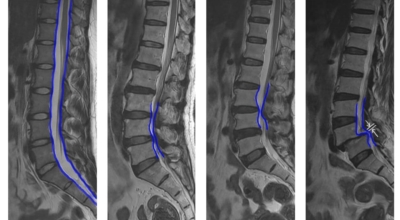

요추관 협착증은 척추 내 신경이 지나가는 통로가 좁아지는 현상으로 기인해서 신경이 눌리면서 이에 따른 여러가지 증상을 유발하는 질환을 의미해요.

허리 협착증은 척추관이 좁아지게 되면서 신경을 압박하게 되어 허리통증과 또한 다리에도 여러가지 증상을 일으키게 되는데, 발생 원인은 주로 노화로 인한 퇴행성 변화가 많았지만 요즈음는 옳지 않은 자세로 오랫동안 앉아있는 사람들이 많아지면서 생기는 경우도 많아졌으며, 선천적인 요인으로 나타나는 경우도 있답니다.